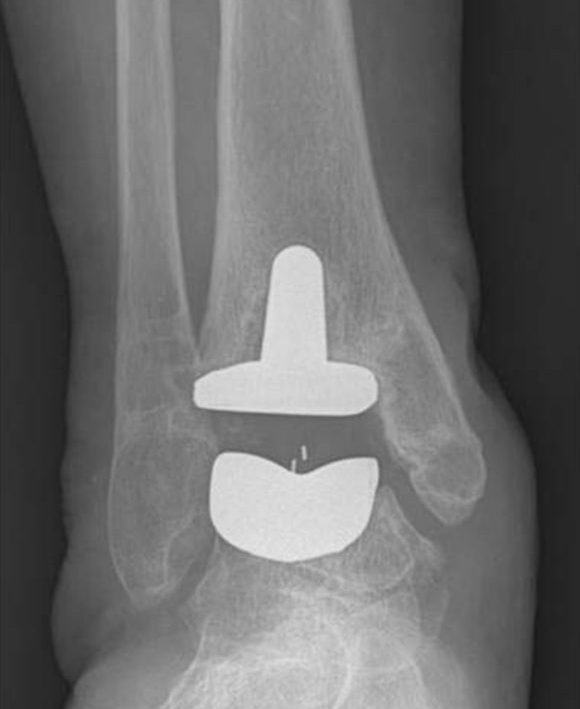

Ankle Replacement

Total ankle replacement (also called ankle arthroplasty) is a surgical option for patients with arthritis of the ankle in old age. This operation can relieve pain and maintain motion in the arthritic ankle joint and is an alternative to arthrodesis (ankle fusion) which can relieve pain but eliminates motion in the joint. Although it does not have the same long-term track record of hip or knee replacement, ankle replacement looks very promising for future

Xray picture of total ankle replacement